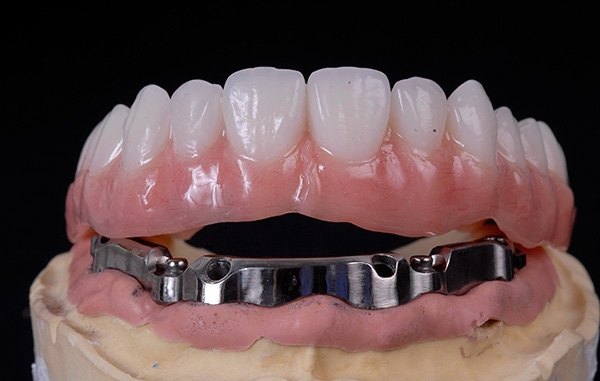

A foto abaixo mostra um exemplo de aparência da dentadura ao usar as duas tecnologias - All-on-4 e All-on-6: